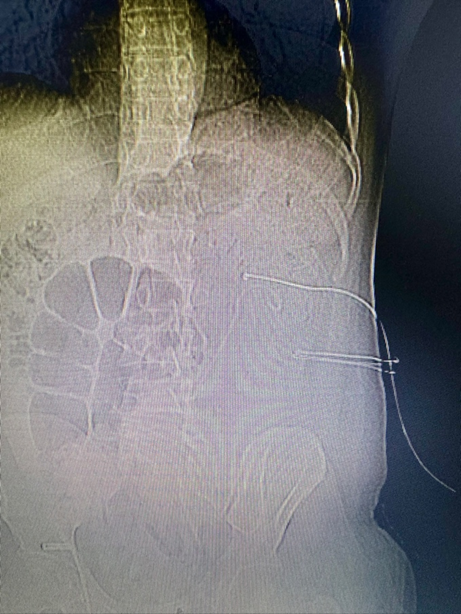

手术经过:郑鑫医生团队在详尽检查和术前评估后,为龚先生实施了经皮肾镜碎石取石手术,在麻醉科的精密配合下,手术非常成功。通过仅一个穿刺通道,医生团队清除了所有结石,实现了患者的完全康复。手术后,龚先生迅速恢复,第二天即撤除造瘘管,第三天顺利出院。

术前与术后复查对比

鹿角型结石是因其形状类似鹿的角而得名,通常由感染性结石组成,填满肾脏内部。传统治疗方法是经皮肾镜碎石取石术,但充满型的鹿角型结石往往需要多通道或多次手术才能彻底清除。鹿角型结石由于其独特的形状和分布,传统上需要多通道或多次手术进行治疗。这类结石通常由感染引起,完全清除对预防复发至关重要。郑鑫医生团队的丰富经验和精湛技艺,单通道手术不仅降低了对肾脏的损害风险,还减少了患者的经济负担。